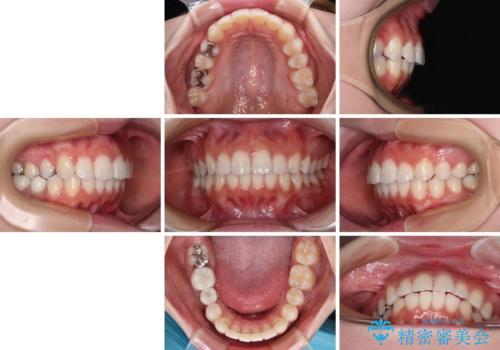

上顎歯列全体を後方移動させたことで唇に当たる感覚は改善され、更には上下の正中位置も合わせることができました。